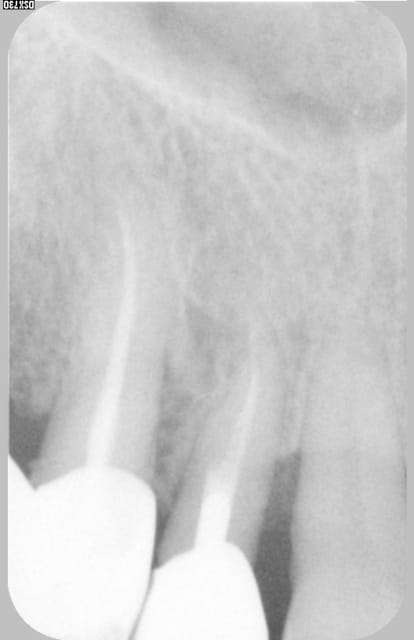

Excusez moi de revenir dans ce débat à fleurets non mouchetés, mais guttaman, qu'est ce en fait. Il y avait une patiente au début de ce post, non ?

Et la soluce est.......poche en linguale...la preuve sur la RX. Comme quoi, même en cherchant une fois, ça suffit pas toujours. Dans le cas présent, la sonde m'a induit en erreur...mais pas le cône de gutta !! (encore une raison d'adorer ce matériau ! ;-) )

Pour le traitement : pour l'instant, abstention thérapeutique car il y a d'autres soucis (cf 2° radio jointe, qui n'est qu'un exemple). Et en plus je sais pas trop quoi lui proposer pour une poche comme ça.

La patiente à une hygiène très correcte, d'autres problèmes paro localisés et c'est une dent support de crochet...

Donc soit purement parodontal sans que la dent y soit pour quelque chose, soit fêlure longitudino-transversale qui crée une sorte de fistule desmodontale en regard.

Même si la dent n'est pas sensible aux variations thermiques, je penche pour cette deuxième possibilité (d'où abstention thérapeutique pour l'instant).